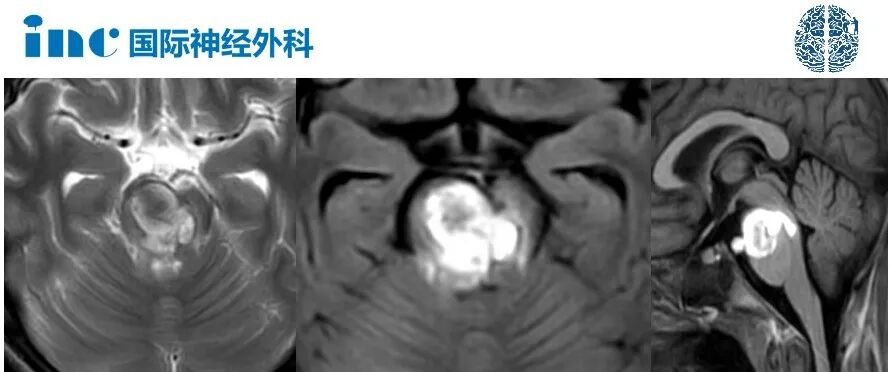

根据小奈术前的核磁,一个大的出血性病变位于桥脑腹侧靠上部位,并伴有周围内源性水肿。这意味着,这是一个相当严重和危险的病变,而这一结果也在小奈此刻的临床症状上有所反映。而且由于小奈出现了吞咽困难,也会存在吸入性肺炎的危险。